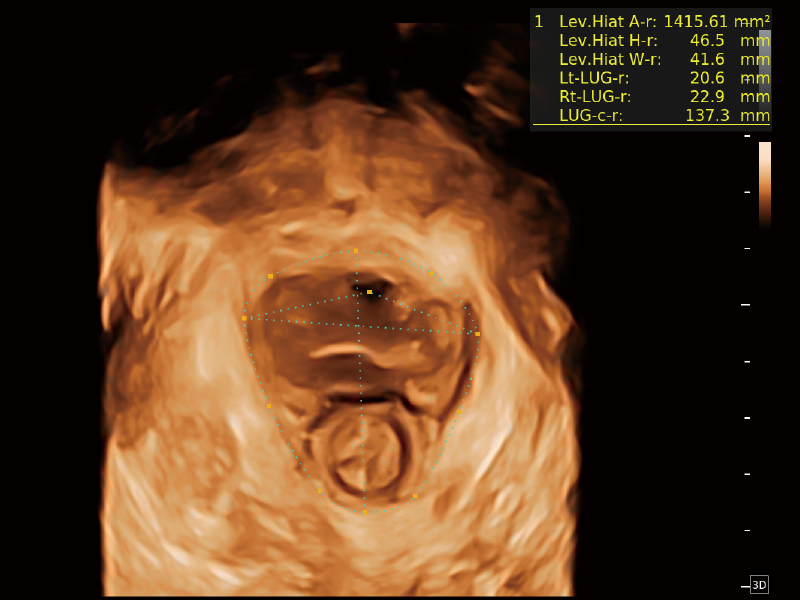

作為開立醫(yī)療全新打造的超高端旗艦超聲產(chǎn)品,從探頭抬起喚醒開啟掃查到多維探頭發(fā)射接收,通過先進(jìn)的場(chǎng)成像發(fā)射、自適應(yīng)聚合重建等技術(shù),基于RF Data原始射頻數(shù)據(jù)在圖像生成、高端功能等方面實(shí)現(xiàn)突破,為婦產(chǎn)科、兒科提供全方位臨床解決方案。

夢(mèng)溪?P80以“關(guān)愛女性”為基石,提供全方位的解決方案,量身定制以滿足女性的健康需求,涵蓋婦科、生殖健康檢查、產(chǎn)前篩查及產(chǎn)后康復(fù)等領(lǐng)域。